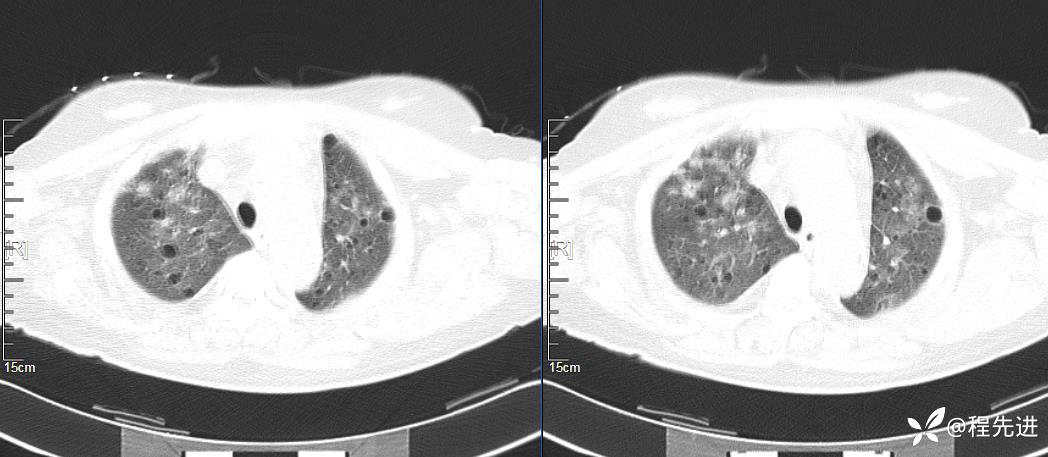

CT平扫(纵隔窗无特殊,就不上传了):

2、本例肺气囊分布有什么特点?肺气囊有无小叶核心?有没有间质纤维化及伴发结节?